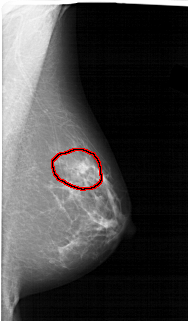

A_1456_1.RIGHT_MLO

LEFT_MLO LINES 6871 PIXELS_PER_LINE 3121 BITS_PER_PIXEL 12 RESOLUTION 43.5 NON_OVERLAY

FILE: A_1456_1.RIGHT_MLO.OVERLAY

TOTAL_ABNORMALITIES 1

ABNORMALITY 1

LESION_TYPE MASS SHAPE IRREGULAR MARGINS ILL_DEFINED

ASSESSMENT 4

SUBTLETY 2

PATHOLOGY BENIGN

TOTAL_OUTLINES 1

BOUNDARY